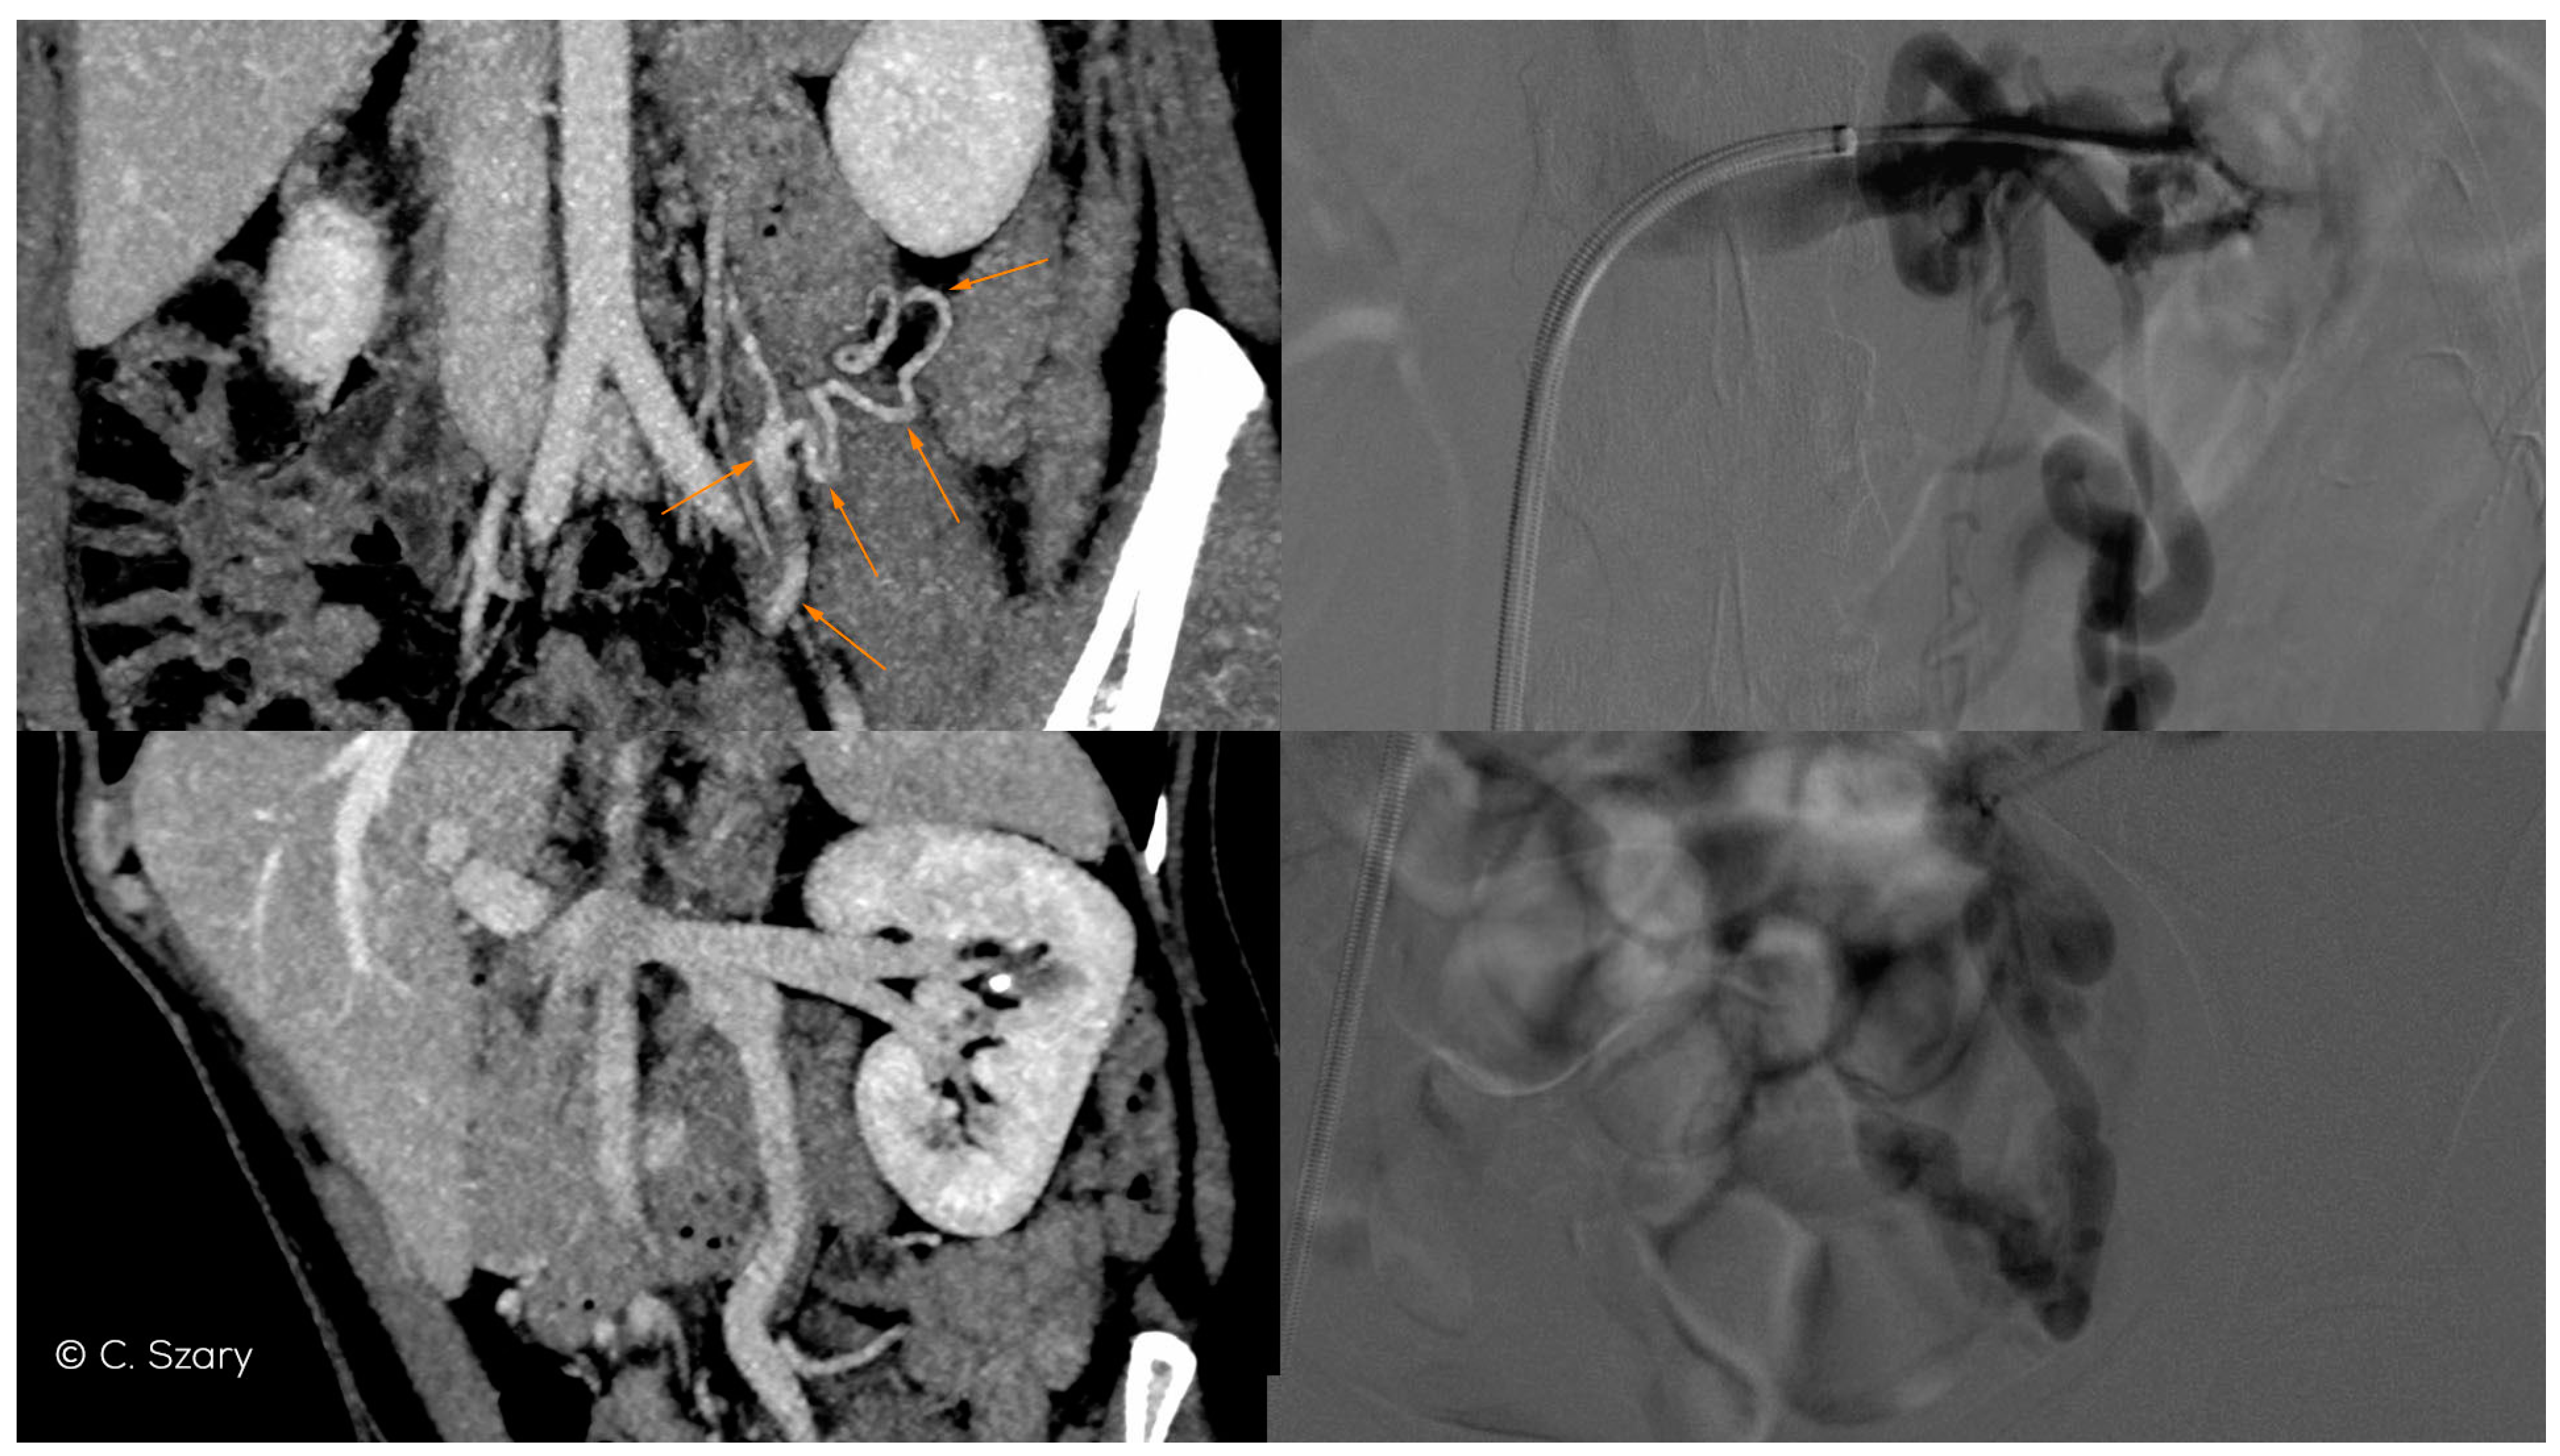

Figure 6.

CTV and intra-interventional phlebographic images of nutcracker phenomenon (LRV compression by superior mesenteric artery, dilated venous collaterals from hilar veins of left kidney (orange arrows), insufficient LOV).